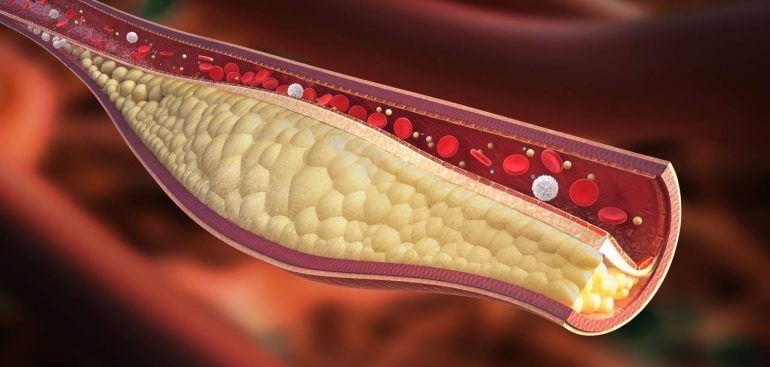

A dislipidemia é um distúrbio caracterizado pelo desequilíbrio nas taxas de colesterol e triglicerídeos no sangue, aumentando o risco de entupimento das artérias e doenças